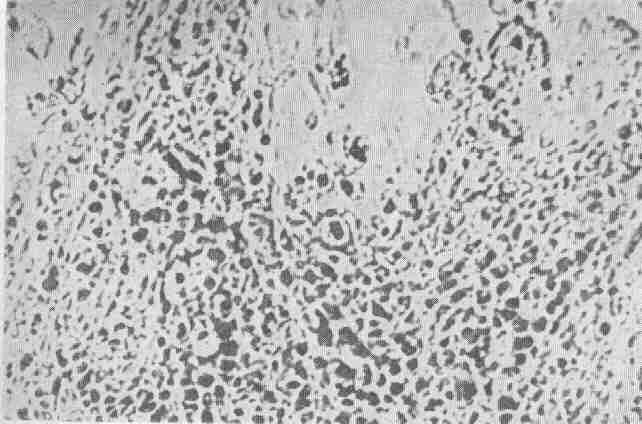

Obserwowany

pod mikroskopem tworzy struktury krystaliczne podobne do ,,mrozu na szybie"

lub ,,liści paproci". Jego szczególna struktura pozwala na przenikanie

plemników z pochwy do wnętrza macicy. Dlatego w dalszym opisie będzimy

go nazywać śluzem przenikalnym.